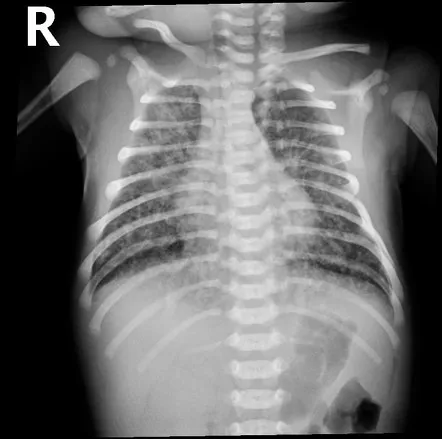

- CXR: Ground-glass pattern, air bronchograms.

- CXR: Perihilar streaks, fissural fluid, hyperinflation. Resolves <72 hrs.

- CXR: Patchy infiltrates, hyperinflation.

- CXR: Diffuse infiltrates, consolidation.

- RDS (HMD): In preterms due to surfactant deficiency. CXR: ground-glass opacities, air bronchograms.

- TTN: In term/late preterm (post-C-section) from delayed lung fluid clearance. CXR: perihilar streaking. Resolves 24-72h.

- MAS: In post-term/stressed infants due to meconium aspiration. CXR: patchy infiltrates, hyperinflation.

- Congenital Pneumonia: Early onset, often GBS. CXR variable.